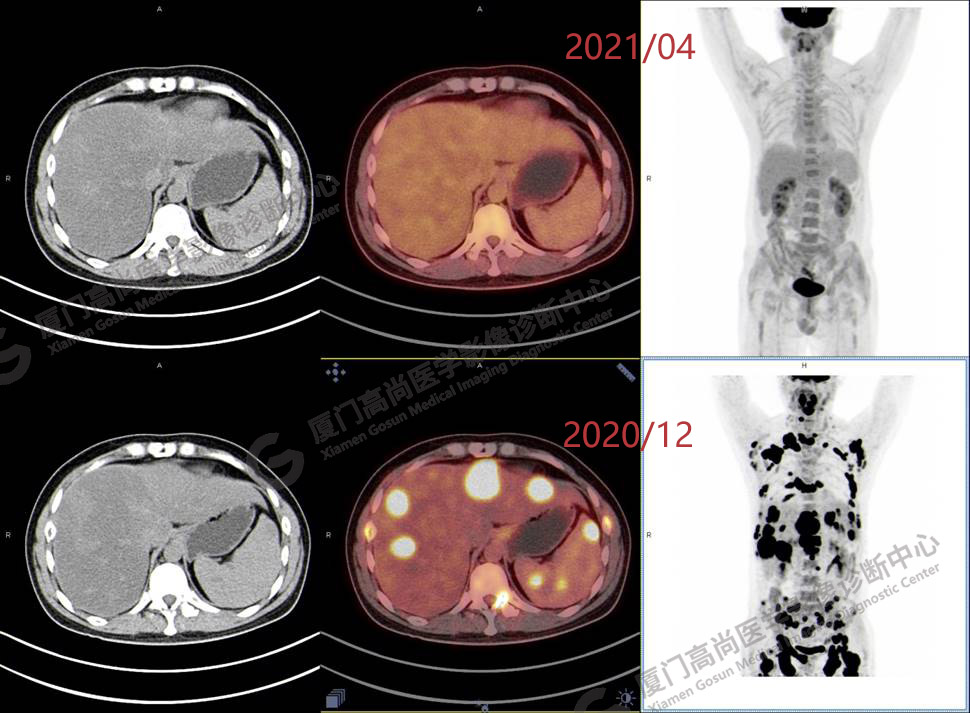

2020.12月本中心PET/CT示:全身多發(fā)腫大淋巴結(jié),代謝不同程度增高;肝臟多發(fā)稍高密度結(jié)節(jié)、脾臟多發(fā)稍低密度結(jié)節(jié),代謝異常增高;全身多發(fā)骨骼溶骨性骨質(zhì)破壞,代謝異常增高,胸2、腰1椎體病理性骨折,診斷為淋巴瘤。隨后,病理確診為彌漫大B細(xì)胞淋巴瘤。

患者化療4個(gè)療程后,于2021.04月返我中心復(fù)查,現(xiàn)患者本人已能自主行走,此次更是獨(dú)自一人來我中心復(fù)查PET/CT。檢查結(jié)果顯示:原全身多發(fā)病灶基本消失,且病灶代謝基本恢復(fù)正常。以下是患者PET/CT前后對(duì)比圖像:

PET/CT前后對(duì)比圖像4